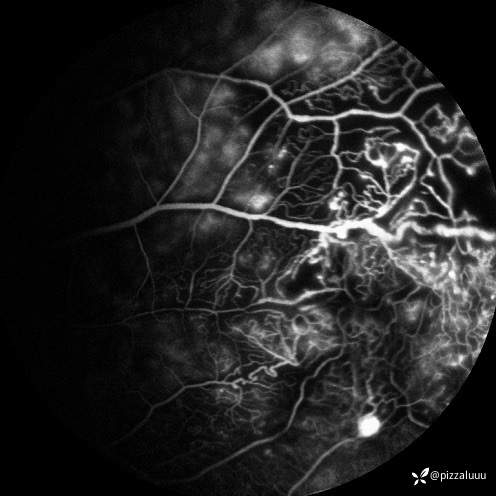

今天补充了FFA、AF和眼底照相。很典型的coats,后极部视网膜可见块状不规则而隆起的黄色渗出。AF可见病灶处低自发荧光。FFA所见:视网膜毛细血管扩张迂曲及异常血管形态,以小动脉明显,管壁呈囊样扩张,有梭形、串珠样动脉瘤。大片无灌注区。异常血管早期渗漏明显,形成强荧光斑,晚期荧光融合。由于大片黄白色渗出位于外丛状层,对视网膜血管荧光影响不大。可看到脉络膜背景荧光遮蔽。